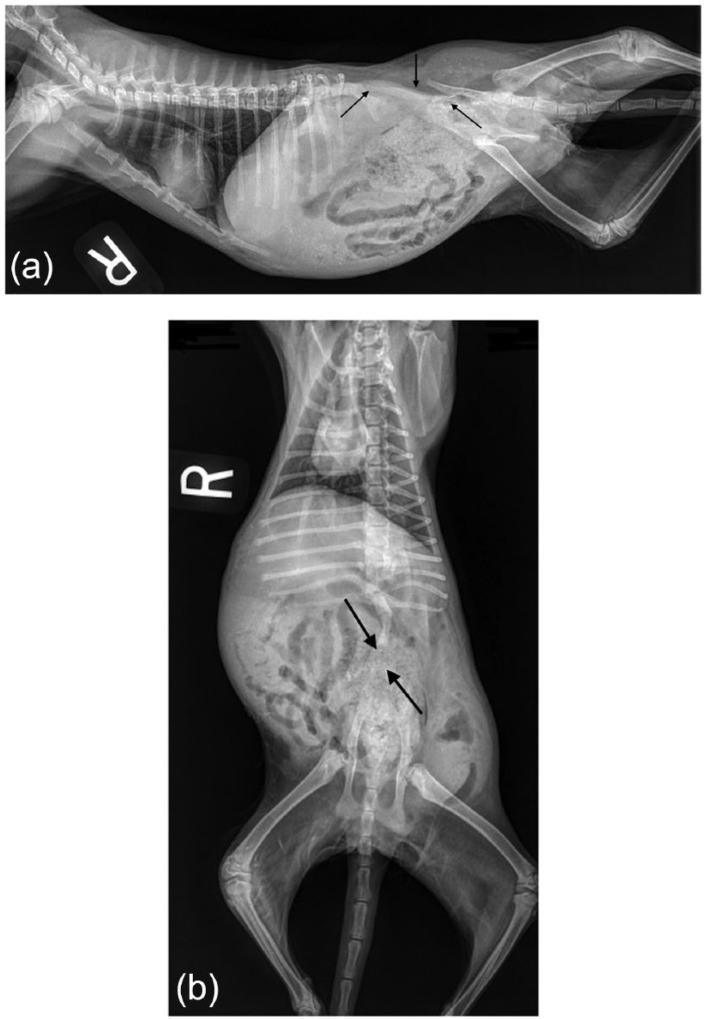

Lumbosacral agenesis is a rare congenital condition reported in children. We report a 17-week-old female domestic shorthair cat with lumbosacral agenesis on whole-body radiographs. The cat was euthanized shortly thereafter presentation. A necropsy was not permitted.

腰骶部发育不全是一种在儿童中报道的罕见先天性疾病。我们报告了一只17周龄的雌性家猫,全身X光片显示有腰骶部发育不全。该猫在出现症状后不久实施了安乐死。未进行尸检。